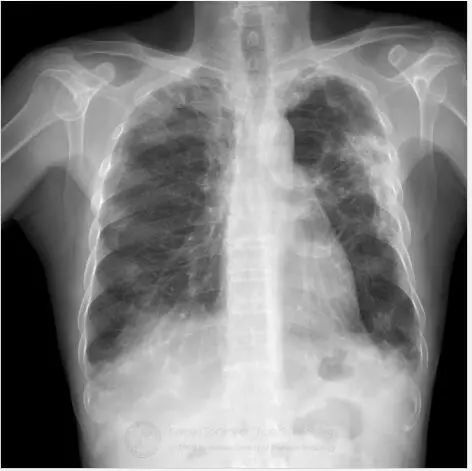

初始胸片显示双肺斑片状或外周实变,以及磨玻璃影。胸部CT显示双肺多灶性、斑片状实变,伴中央空气支气管征,以及外周磨玻璃影。病变在外周、上叶多见。

鉴别诊断:包括慢性嗜酸粒细胞性肺炎、隐源机化性肺炎和Churg-Strauss综合征。

诊断:慢性嗜酸粒细胞性肺炎